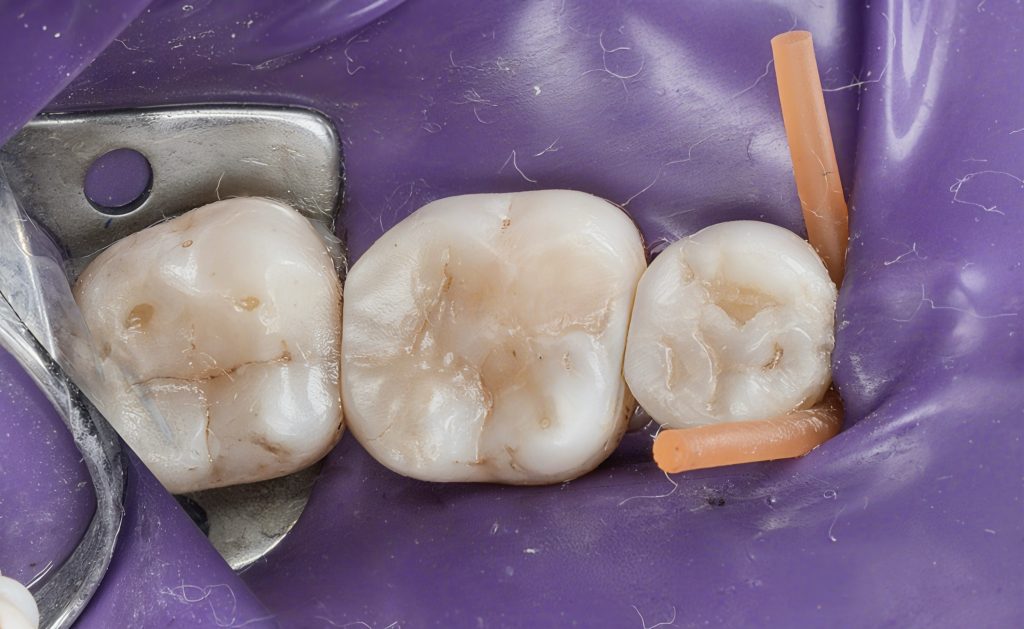

Polishing and Final Result

Image 15–16:

“Pre-polish with Estelite Pogo. High-gloss achieved using Diashine and Lucida by Style Italiano.”

Image 17 (Final):

“Final restorations showing natural morphology, tight proximal contacts, and enamel-like gloss.”